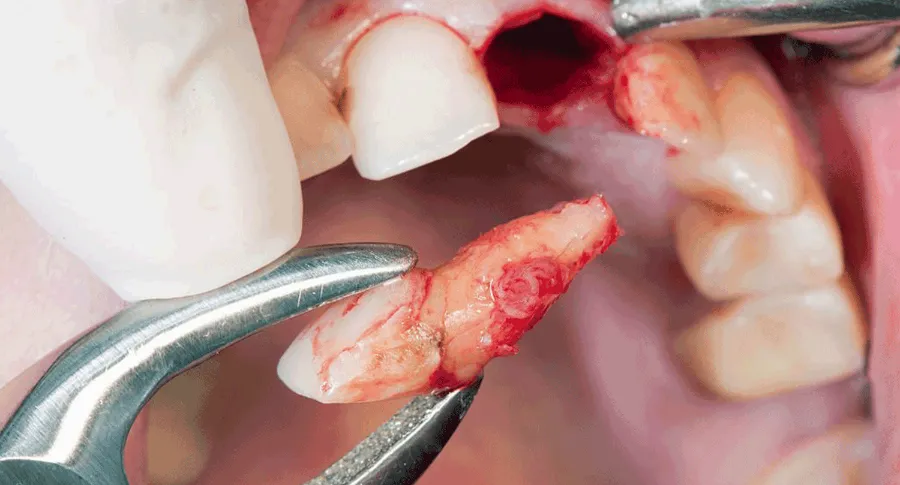

There are two types of tooth extractions: simple and surgical.

Simple extractions are typically performed on teeth that are visible and easy to access, while surgical extractions are more complex and involve cutting into the gum tissue.

They will then use special tools, such as forceps, to loosen the tooth from its socket and remove it.